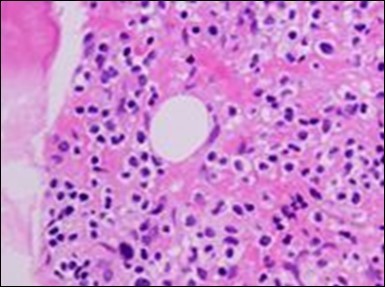

Figure 2.HCL: hairy cells with projecting cytoplasm abutting bony trabaculae(18).

The classic hairy cell is medium sized with a magnitude of 10-14µm. The moderately abundant or variable cytoplasm may be transparent or mildly basophilic. The cellular surface with the characteristic serrated perimeter depicts innumerable fragile or stout extensions of cytoplasm ,particularly discernible on the phase contrast and electron microscopy. The cytoplasm may exhibit vacuoles with occasional azurophilic granules4. The nucleus may be elliptical or reniform, folded or indented with a coarse, reticulated or a finely dispersed chromatin and inconspicuous nucleoli along with infrequent mitosis. Bone marrow aspiration or bone marrow trephine biopsy may be inadequate for diagnosis in 30%-50% individuals4. The trephine sections of the bone marrow may depict a characteristic interstitial pattern of leukaemic infiltration. Generally the bone marrow is hyper-cellular, though it may be hypo-cellular in 10-15% individuals4. The leukaemia cell ingress may be diffuse or partial, although diffuse infiltration is frequent. The partial variety of leukaemic dissemination may be ineptly categorized with an indeterminate differentiation from the uninvolved marrow. The malignant insertions may initially emerge as miniature, undefined, cellular loci. The formalin fixed, paraffin embedded sections may elucidate a crystalline zone or a “halo” appearance of the cells with a circumscribed nucleus on account of the plentiful cytoplasm4. The cellular margins may be intertwined. Fixation of bone marrow smears with Zenker’s fixative may demonstrate a retracted cytoplasm of the hairy cells with a consequent disconnected structure. The bone marrow in the absence of a malignant process may be hypo-cellular or hyper-cellular. Reticulin stains may delineate an enhanced accrual of broad, dense reticulum fibres surrounding the aggregates of leukaemia cells with the fibrous circumlocution of individual malignant cell and fibrotic extensions into the abutting, uninvolved bone marrow4.

The leukaemia cells may enunciate a characteristic immune phenotype, crucial for a confirmatory diagnosis. The peripheral blood mononuclear B cell population may display a kappa or lambda light chain restriction. The phenotype of classic hairy cell leukaemia may be delineated by concurrent, immune reactive CD19+ CD20+,CD 11c+, CD25+, CD103+ and CD123+. An intensely immune reactive CD200+ and a non reactive CD27- antigen may be present2, 4. Evaluation of a trephine bone marrow biopsy and bone marrow aspirate may define the degree of tumour infiltration. A dry tap on account of prominent bone marrow fibrosis may be elucidated at preliminary diagnosis. A decline in the normal haematopoiesis may account for a hypo-cellular marrow in 10% instances. Gradation of cellular infiltrating of the leukaemia within the bone marrow may be appropriately investigated with immune –histochemical stains2, 4. Immune staining for CD20+, annexin 1 and VE1 (a BRAF V600E stain] may validate the diagnosis and precisely analyse the extent of malignant bone marrow infiltration[8]. Determination of BRAF V600E mutation may be critical in therapeutically non responsive individuals with applicable standard therapy or in instances of multitudinous reoccurrences[9]. Deploying inhibitors of BRAF V600E gene may be efficacious in patients impervious to approved therapy. The mutation necessitates a comprehensive scrutiny of the implicated individuals with a sensitive molecular assay which may discern up to < 10% of the hairy leukaemia cells appearing in the peripheral blood smears or bone marrow aspirates diluted with peripheral blood or aspirates elucidating a dry tap[2,4]. Allele specific polymerase chain reaction (PCR) or a next generation sequencing may be optimally employed to circumvent false negative outcomes. If the leukaemia cells are sparse or if particularly sensitive & efficacious molecular techniques are not accessible, the application of appropriate immune histochemical stains to the bone marrow biopsy such as a BRAF V600E mutation stain (VE1) may detect the hairy cells and conclusively diagnose the condition[2,4,10]. Figure 1, Figure 2, Figure 3, Figure 4, Figure 5, Figure 6, Figure 7, Figure 8, Figure 9, Figure 10, Figure 11, Figure 12, Figure 13, Figure 14.